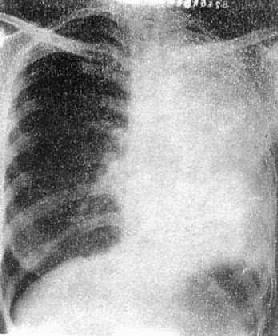

(1)一侧性肺不张:X线现为患侧肺野均匀致密,纵隔向患侧移位,肋间隙变窄(图3-1-7)。健侧肺可有代偿性肺气肿。

一侧性肺不张

图3-1-7 一侧性肺不张

左侧支气管阻塞引起左侧全肺不张,显示左侧肺野均匀致密,

纵隔向患侧移位,肋间隙变窄,膈升高